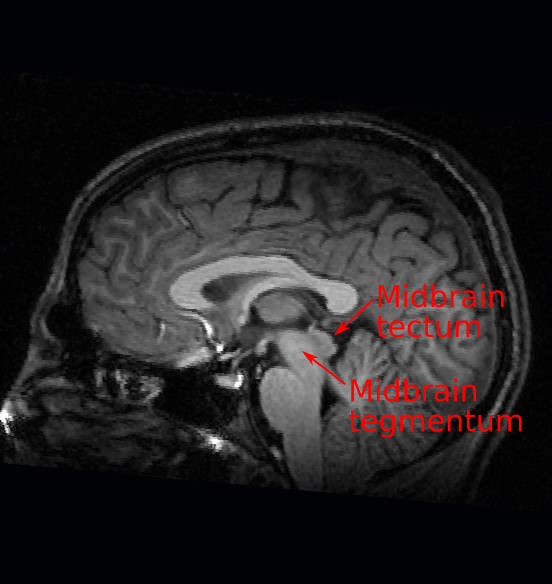

Midbrain

Note:

The tectum of the midbrain, which is latin for ‘roof’ contains the superior and inferior colliculi and is important for processing visual and auditory information as well as shaping motor commands for orienting the head and body.

- red nucleus is part of midbrain, without a corticospinal tract it controls gait. Baby crawling controlled by red nucleus. Arm swinging while walking

Ventral to the cerebral aqueduct through which cerebral spinal fluid circulates, you will find the tegmentum of the midbrain which contains the —>

--

Parkinson’s- loss of dopamine making neurons in the midbrain's substantia nigra

Note:

substantia nigra pars compacta, a nucleus containing neurons making the neurotransmitter dopamine that are important for regulating motor movements via their connections with the basal ganglia and which are devastated in parkinson’s disease.

dark appearance due to high levels of dark pigment neuromelanin in dopaminergic neurons

Neuromelanin is directly biosynthesized from L-DOPA, precursor to dopamine, by tyrosine hydroxylase (TH)